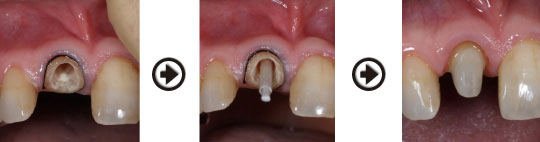

前歯にファイバーコアを入れ、オールセラミッククラウンを被せた症例

歯内療法をした後、グラスファイバー系のコア(土台)を入れました。利点として、歯根破折を起こしにくい、光の透過性が天然歯に近い、金属を使わないので歯肉に影ができないなど、美しく、自然な仕上がりとなります。